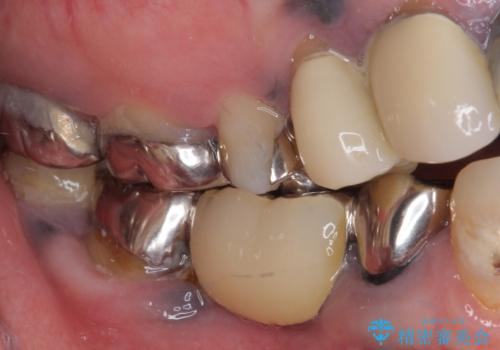

- 全顎的に銀歯が多く、その中でも目立って気になる奥歯のブリッジをセラミックに替えたいとのことで来院された患者様です。

上顎のブリッジを先に交換したものの、今度は下顎のブリッジ支台歯が食事もできないほど痛み出したとのことでした。

銀歯の適合が悪く、土台の歯に虫歯多く残っていたので、痛む歯の根管治療とファイバーコアによる土台植立を行い、フルジルコニア製ブリッジを装着することとしました。